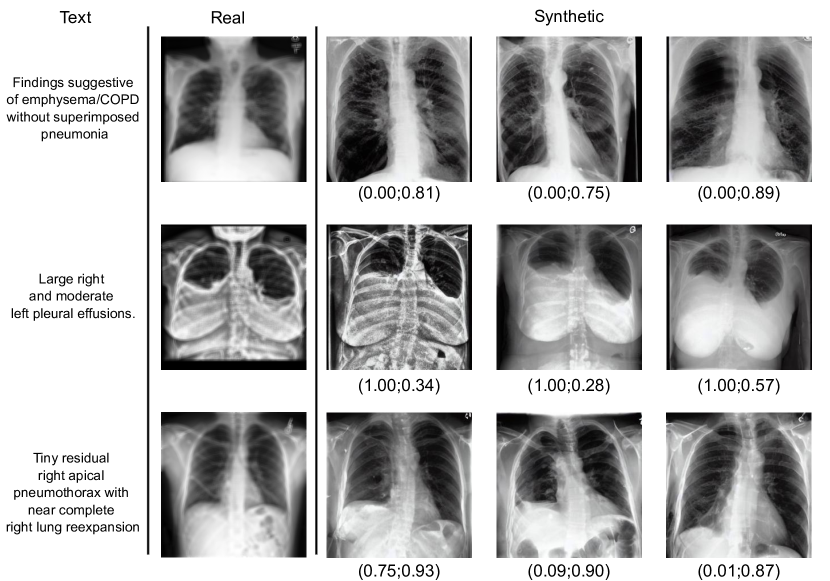

Refer to caption

(b) We display several synthetic images along with their prompt and real image associated with the prompt. We show below the synthetic images the re-identification score and text-to-image similarity in the format (sreid;salign)subscript𝑠𝑟𝑒𝑖𝑑subscript𝑠𝑎𝑙𝑖𝑔𝑛(s_{re-id};s_{align}). In the first row, the synthetic images do not contain any identifiable information about the real image while corresponding fairly well to the text description. In the second row, all synthetic images contain identifiable information, despite having a different style/contrast. The bottom row displays synthetic images with good text alignment but some contain identifiable information and some do not.

Figure 5: Illustration showing how synthetic images, obtained by using the same prompt of the real image as conditioning, relates to the real image as well as the prompt. We try to mitigate privacy risks in these illustrations because the license of MIMIC-CXR 777https://physionet.org/content/mimic-cxr/view-license/2.0.0/ does not allow sharing data. In 5(a), the “Real” image is actually a synthetic image that is very similar to the original image. In 5(b), we blurred the real images.